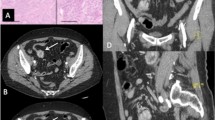

Gastric schwannoma (GS) is usually a benign, neurogenic, and mesenchymal neoplasm derived from the Schwann cells of the Auerbachs nerve plexus, with an incidence rate of 2–17% (Choi et al. 2012). Gastric gastrointestinal tumors (GISTs) originating from the interstitial cells of Cajal have the highest incidence rate among mesenchymal tumors, accounting for 60–70% of occurrences (Gao et al. 2017; Tsuboi et al. 2021). GSs and GISTs share a similar affected population, clinical symptoms, and even computed tomography (CT) imaging characteristics, particularly in large (> 5 cm) tumors (Hong et al. 2008; Ji et al. 2015; Levy et al. 2003; Wang et al. 2019a, b). However, the treatment strategies and prognoses for these two tumors differ substantially. GS, which is almost always a benign tumor, has an excellent prognosis after surgery (Cai et al. 2016). By contrast, GISTs appear potentially malignant and require complete excision. Furthermore, high-risk GISTs should receive imatinib treatment as adjuvant or neoadjuvant therapy (Casali et al. 2022; Li et al. 2017). It is of great clinical significance to accurately distinguish these two tumors preoperatively.

All CT images were independently retrospectively reviewed and evaluated by two associate chief radiologists (Radiologist 1 with 13 and Radiologist 2 with 15 years of experience in abdominal imaging). The two physicians were blinded to the surgical and pathological data of each patient, and the final conclusions were achieved through consensus decisions. The evaluated CT features consisted of qualitative and quantitative variables. Qualitative variables included location (cardia, fundus, body, or antrum), grow pattern (endophytic, exophytic, or mixed), contour (round, oval, or irregular), necrosis, calcification, surface ulceration, lymph node (LN), hemorrhage, peritumoral exudation, necrosis under the tumor wall, and intratumoral vessel. Quantitative variables included the CT attenuation value on unenhanced phase (CTU), arterial phase (CTA), and portal venous phase (CTV) imaging, the degree of enhancement on arterial phase (DEAP; DEAP = CTA – CTU) and portal venous phase (DEPP; DEPP = CTV − CTU) imaging, long diameter (LD), short diameter (SD), and the ratio of long diameter to short diameter (LD/SD). Lymph node was defined as positive when the short diameter of the lymph node was larger than 10 mm.

Two hundred forty-three patients with tumors (forty-three GSs and two hundred GISTs) from Center 1 and fifty-nine patients with tumors (six GSs and fifty-threeGISTs) from Center 2 were included in our series. The clinical baseline characteristics and CT findings of the 302 patients in the training (n = 211) and validation (n = 91) cohorts are listed in Table 1. For both training and validation sets, the number of underlying diseases, lesion location, necrosis, and necrosis under the tumor wall were significant variables in the univariate analysis between the two tumor types, while growth pattern was significantly different in the training cohort. Although patients with GIST were older than those with GS both in training and validation cohorts, the differences were not statistically significant. There were no significant differences in any of the clinical and CT parameters between the two datasets (all p > 0.05), which indicates that the patient allocation to the two datasets was well balanced. The detailed results are summarized in Table 1.

Among the clinical and CT features, sex, LD/SD, location, growth pattern, necrosis, and number of underlying diseases were found to be significant features for the differentiation of GSs from GISTs. GS was more predominantly found in female patients than GIST, which is consistent with the previous studies of Ji et al. (2015), but different to the finding of Xu et al. (2022). We found that GSs tended to grow in the gastric body and antrum, whereas gastric GISTs were often seen in the body and the fundus, which is similar to the findings in Xu et al. (2022) and our previous reports (Wang et al. 2021). An exophytic or mixed growth pattern found in GS in several previous studies (Choi et al. 2012; He et al. 2017; Xu et al. 2022) is also in agreement with our findings. Our study also revealed necrosis to be a significant CT feature suggesting GIST rather than GS, which is in line with the study of He et al. (He et al. 2017). The lack of necrosis in schwannomas may be a result of the slower growth rate of GS compared with GIST (Choi et al. 2014). To our surprise, patients with GIST tended to have more underlying diseases than those with GS, which has not been reported before. The underlying diseases included hypertension, diabetes, cardiovascular disease, cerebrovascular disease, chronic obstructive pulmonary disease, and chronic kidney diseases. The reason for this may be related to the fact that our patients with GIST were older than those with GS, and the possibility of suffering from underlying diseases may increase accordingly. We also speculate that patients with underlying diseases may be more likely to be affected by malignant tumors than benign ones, although this hypothesis still requires more cases and studies to confirm it.